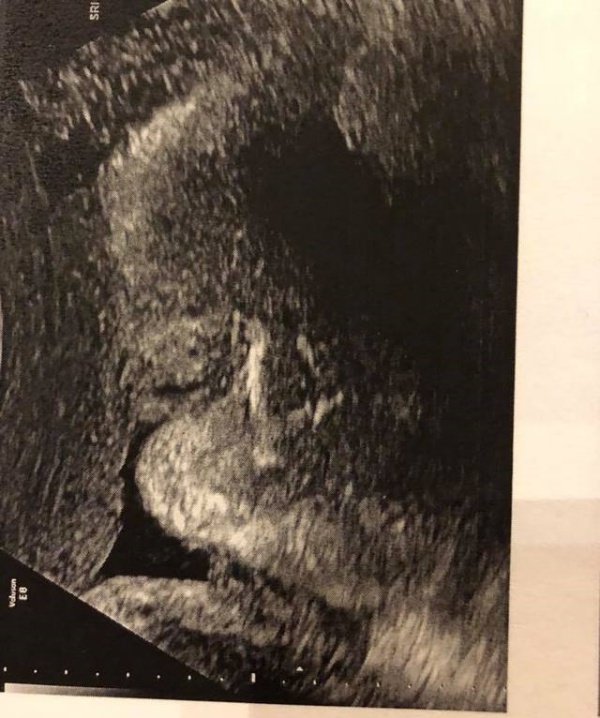

▼隋棠表示,老三Olie正在闭目养神。